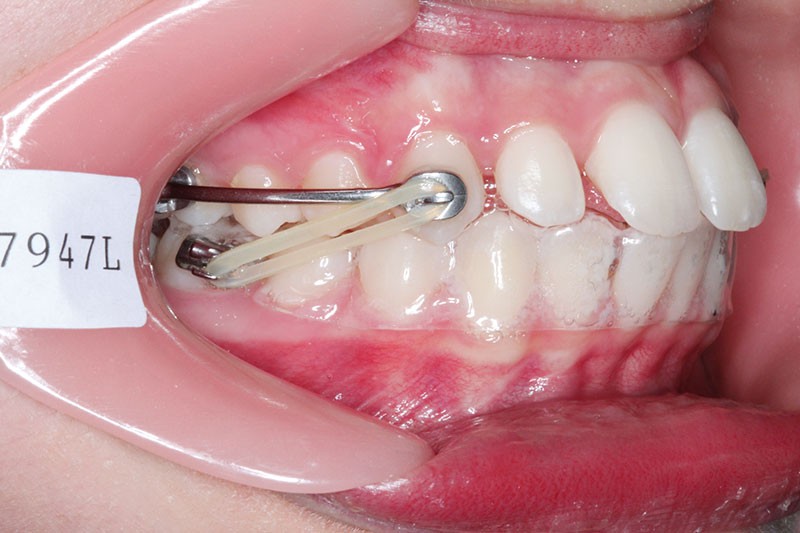

Il a été décidé de mettre en place un système de correction de la classe II “Motion Classe II Carriere” composé de bras latéraux reliant canine et molaire et d’élastiques de classe II ancrés sur des tubes molaires sur 36 et 46 et une gouttière thermoformée portée en permanence. sAprès dérotation des 16 et 26, recul des secteurs latéraux et libération de la croissance mandibulaire nous mettrons en place un système multiattache autoligaturant passif Carriere SLX 022×028 avec la séquence d’arcs suivante :

1re phase : le Motion Appliance Carriere

Afin d’obtenir la correction de la classe II, nous avons fait porter pendant 3 mois une mécanique d’élastiques intermaxillaires, jour et nuit, avec la séquence suivante (fig. 4):

1er mois : élastiques 6oz. ¼”

2e mois et mois suivants : 8 oz. 3/16”